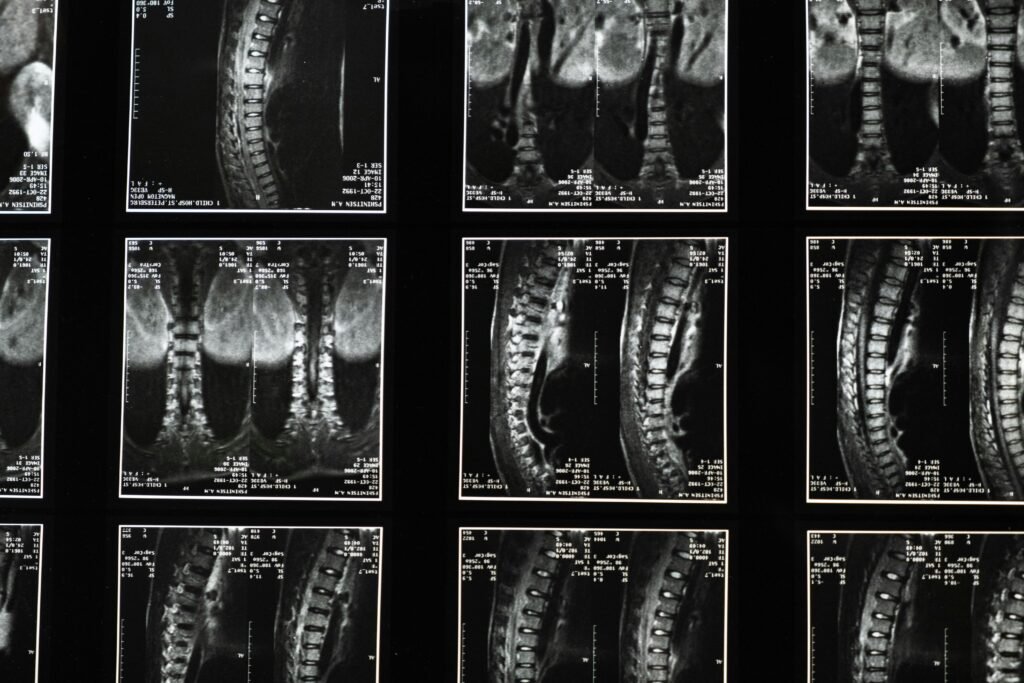

Comprehensive spinal x-ray images, ideal for medical studies and diagnostics.